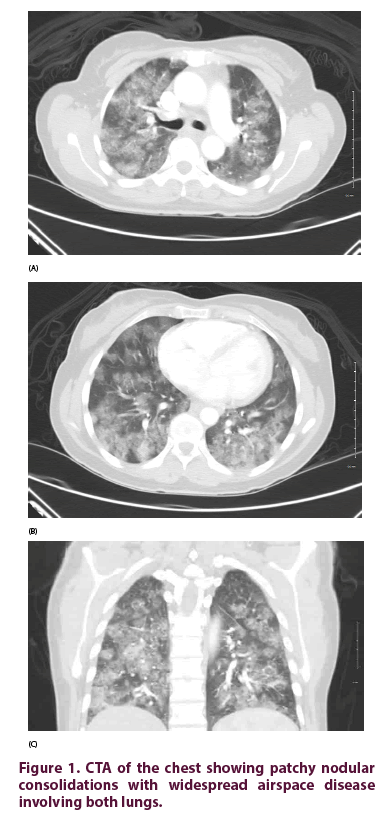

CTA of the chest (Figure 1) showed patchy nodular consolidations with widespread airspace disease involving both lungs, which raised the concern for pneumonia or vasculitis. There was no mediastinal adenopathy. Given initial concern with pneumonia, the patient was started on IV vancomycin and piperacillin-tazobactam empirically and was given 2 units of PRBCs along with Vitamin B12 IM daily for 7 days and ferrous sulfate 325 mg daily. A bronchoscopy was performed and repeated Broncho Alveolar Lavage (BAL) samples indicated alveolar hemorrhage. In the light of suspected vasculitis, she was started on intravenous methylprednisolone 1 g daily.